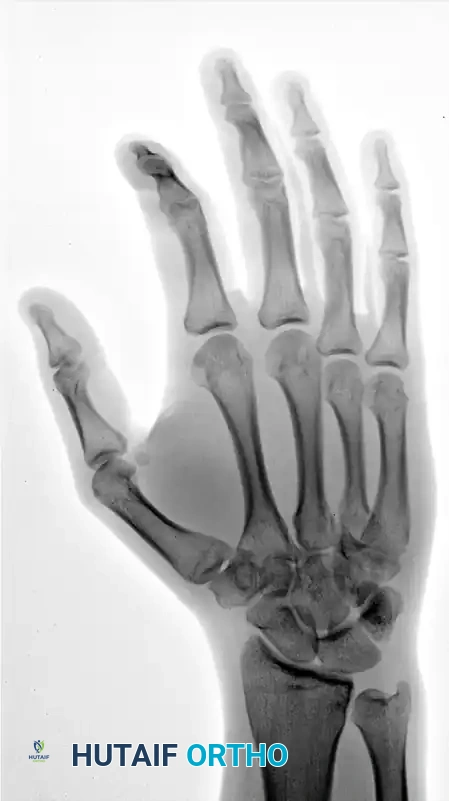

FIGURE 67-30 A: Clinical appearance of the hand before reduction. Note the profound dorsoulnar hand swelling and loss of the normal metacarpal arch consistent with a 4th and 5th CMC dislocation.

Standard posteroanterior (PA), lateral, and oblique radiographs are mandatory. However, the overlapping anatomy of the carpus can obscure subtle subluxations.

FIGURE 67-30 B-D: Posteroanterior, Lateral, and Oblique radiographic views demonstrating the dorsal dislocation of the fourth and fifth carpometacarpal joints.

> CLINICAL PEARL: Always obtain a true lateral radiograph of the hand. The metacarpal shafts should align perfectly parallel. Any dorsal divergence of the 4th or 5th metacarpal shafts relative to the 3rd metacarpal is highly indicative of a CMC dislocation. If plain films are equivocal, a CT scan is the gold standard for evaluating articular comminution and subluxation.